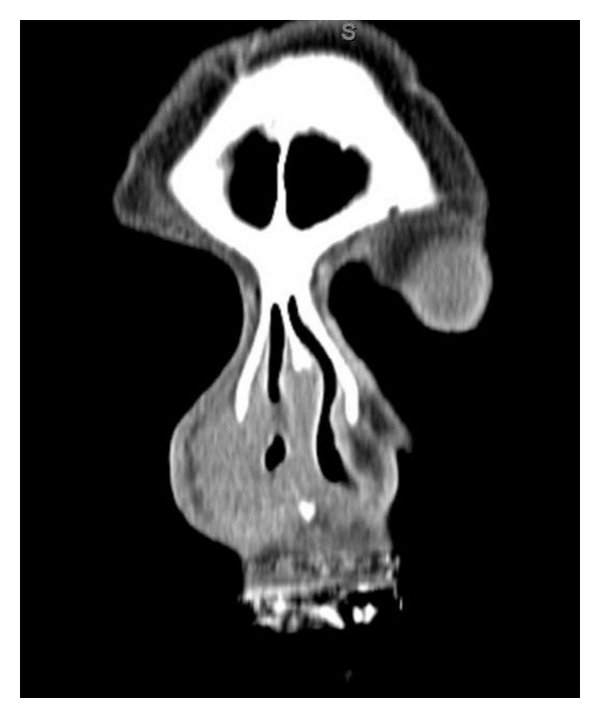

Maxillofacial computed tomography (CT) revealed an extensive nonenhancing submucosal lesion of soft tissue density involving the entirety of the right nasal ala, with associated distortion of the columella due to mass effect. The lesion appeared to be in a subcutaneous plane. The mucosal surface also appeared to be preserved. There was an incidental finding of benign-appearing mucosal thickening seen within the right maxillary and ethmoid sinuses (Figures 1, 2, and 3).

Much of the dilemma with midline destructive lesions of the face is in diagnosis. However, establishing the diagnosis quickly is imperative so that proper therapy can be initiated without delay. As seen with our patient who was initially treated with multiple courses of antibiotics, the diagnostic approach tends to be difficult as symptoms are nonspecific and the differential diagnosis is extensive, including infectious, autoimmune, neoplastic, and inflammatory etiologies. The initial laboratory workup includes a complete blood count with differential. Further testing for specific disease and autoimmune entities may include classic antineutrophil cytoplasmic antibodies (cANCAs), perinuclear antineutrophil antibodies (pANCAs), proteinase 3 (PR3), myeloperoidase (MPO), angiotensin converting enzyme (ACE), rapid plasma reagin (RPR), anti-Sjogren A and B antibodies, rheumatoid factor (RF), coccidioidomycosis, and human immunodeficiency virus (HIV) testing [3]. Imaging usually reveals an infiltrative soft tissue mass that partially obliterates or obstructs the nasal passages (Figure 1). Ultimately, tissue biopsy is required for diagnosis. Fine needle aspiration (FNA) can be attempted but may be nondiagnostic due to the presence of extensive necrosis. Similarly, even biopsy specimens may be difficult to interpret requiring multiple biopsies [1].

The radiologic findings of extensive soft tissue and sinonasal involvement yield a differential diagnosis that includes granulomatosis with polyangiitis (formerly Wegener’s granulomatosis), other granulomatous infections, other non-Hodgkins lymphoma, adenoid cystic carcinoma, olfactory neuroblastoma, melanoma, and squamous cell carcinoma [6, 7]. Overall, the imaging characteristics of NKTL are relatively nonspecific. However, there are features that can suggest the diagnosis. Mild to moderate heterogenous enhancement of the involved soft-tissue on both CT and MRI imaging is generally present. Bony erosion is reportedly present in 40 to 78% of patients with the most common sites being the medial maxillary wall, the nasal septum, and the lamina papyracea. Despite marked soft-tissue involvement of the midface, the anterior maxillary sinus wall is rarely involved. Additionally, the bony involvement of NKTL is less severe than other destructive entities such as sinonasal squamous cell carcinoma. On MRI, tumoral tissue appears isointense on T1-weighted images and hyperintense on T2-weighted sequences. T2-weighted images help differentiate retained secretions (markedly hyperintense) from tumor tissue which is heterogeneously hyperintense [6]. In the case presented, the lesion did not appear to arise from the cutaneous and mucosal surfaces, making the diagnosis of an epithelial neoplasm less likely. In a patient with a subcutaneous nasal soft tissue lesion, this entity should be considered.